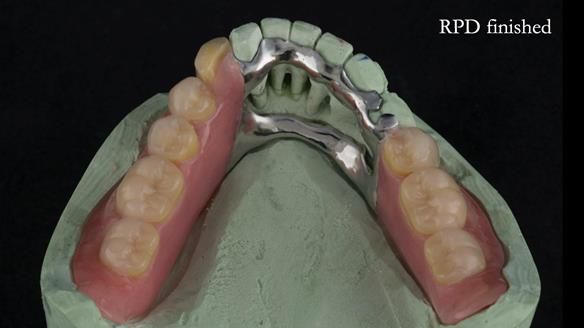

A metal-based upper RPD was made,

with metal backings incorporated to future-proof the design

should further teeth fail.

The way Rowan lengthened the teeth — particularly in the upper RPD — to match the existing gingival recession on the remaining teeth was superb. The dentures sit naturally within the context of the rest of the mouth.